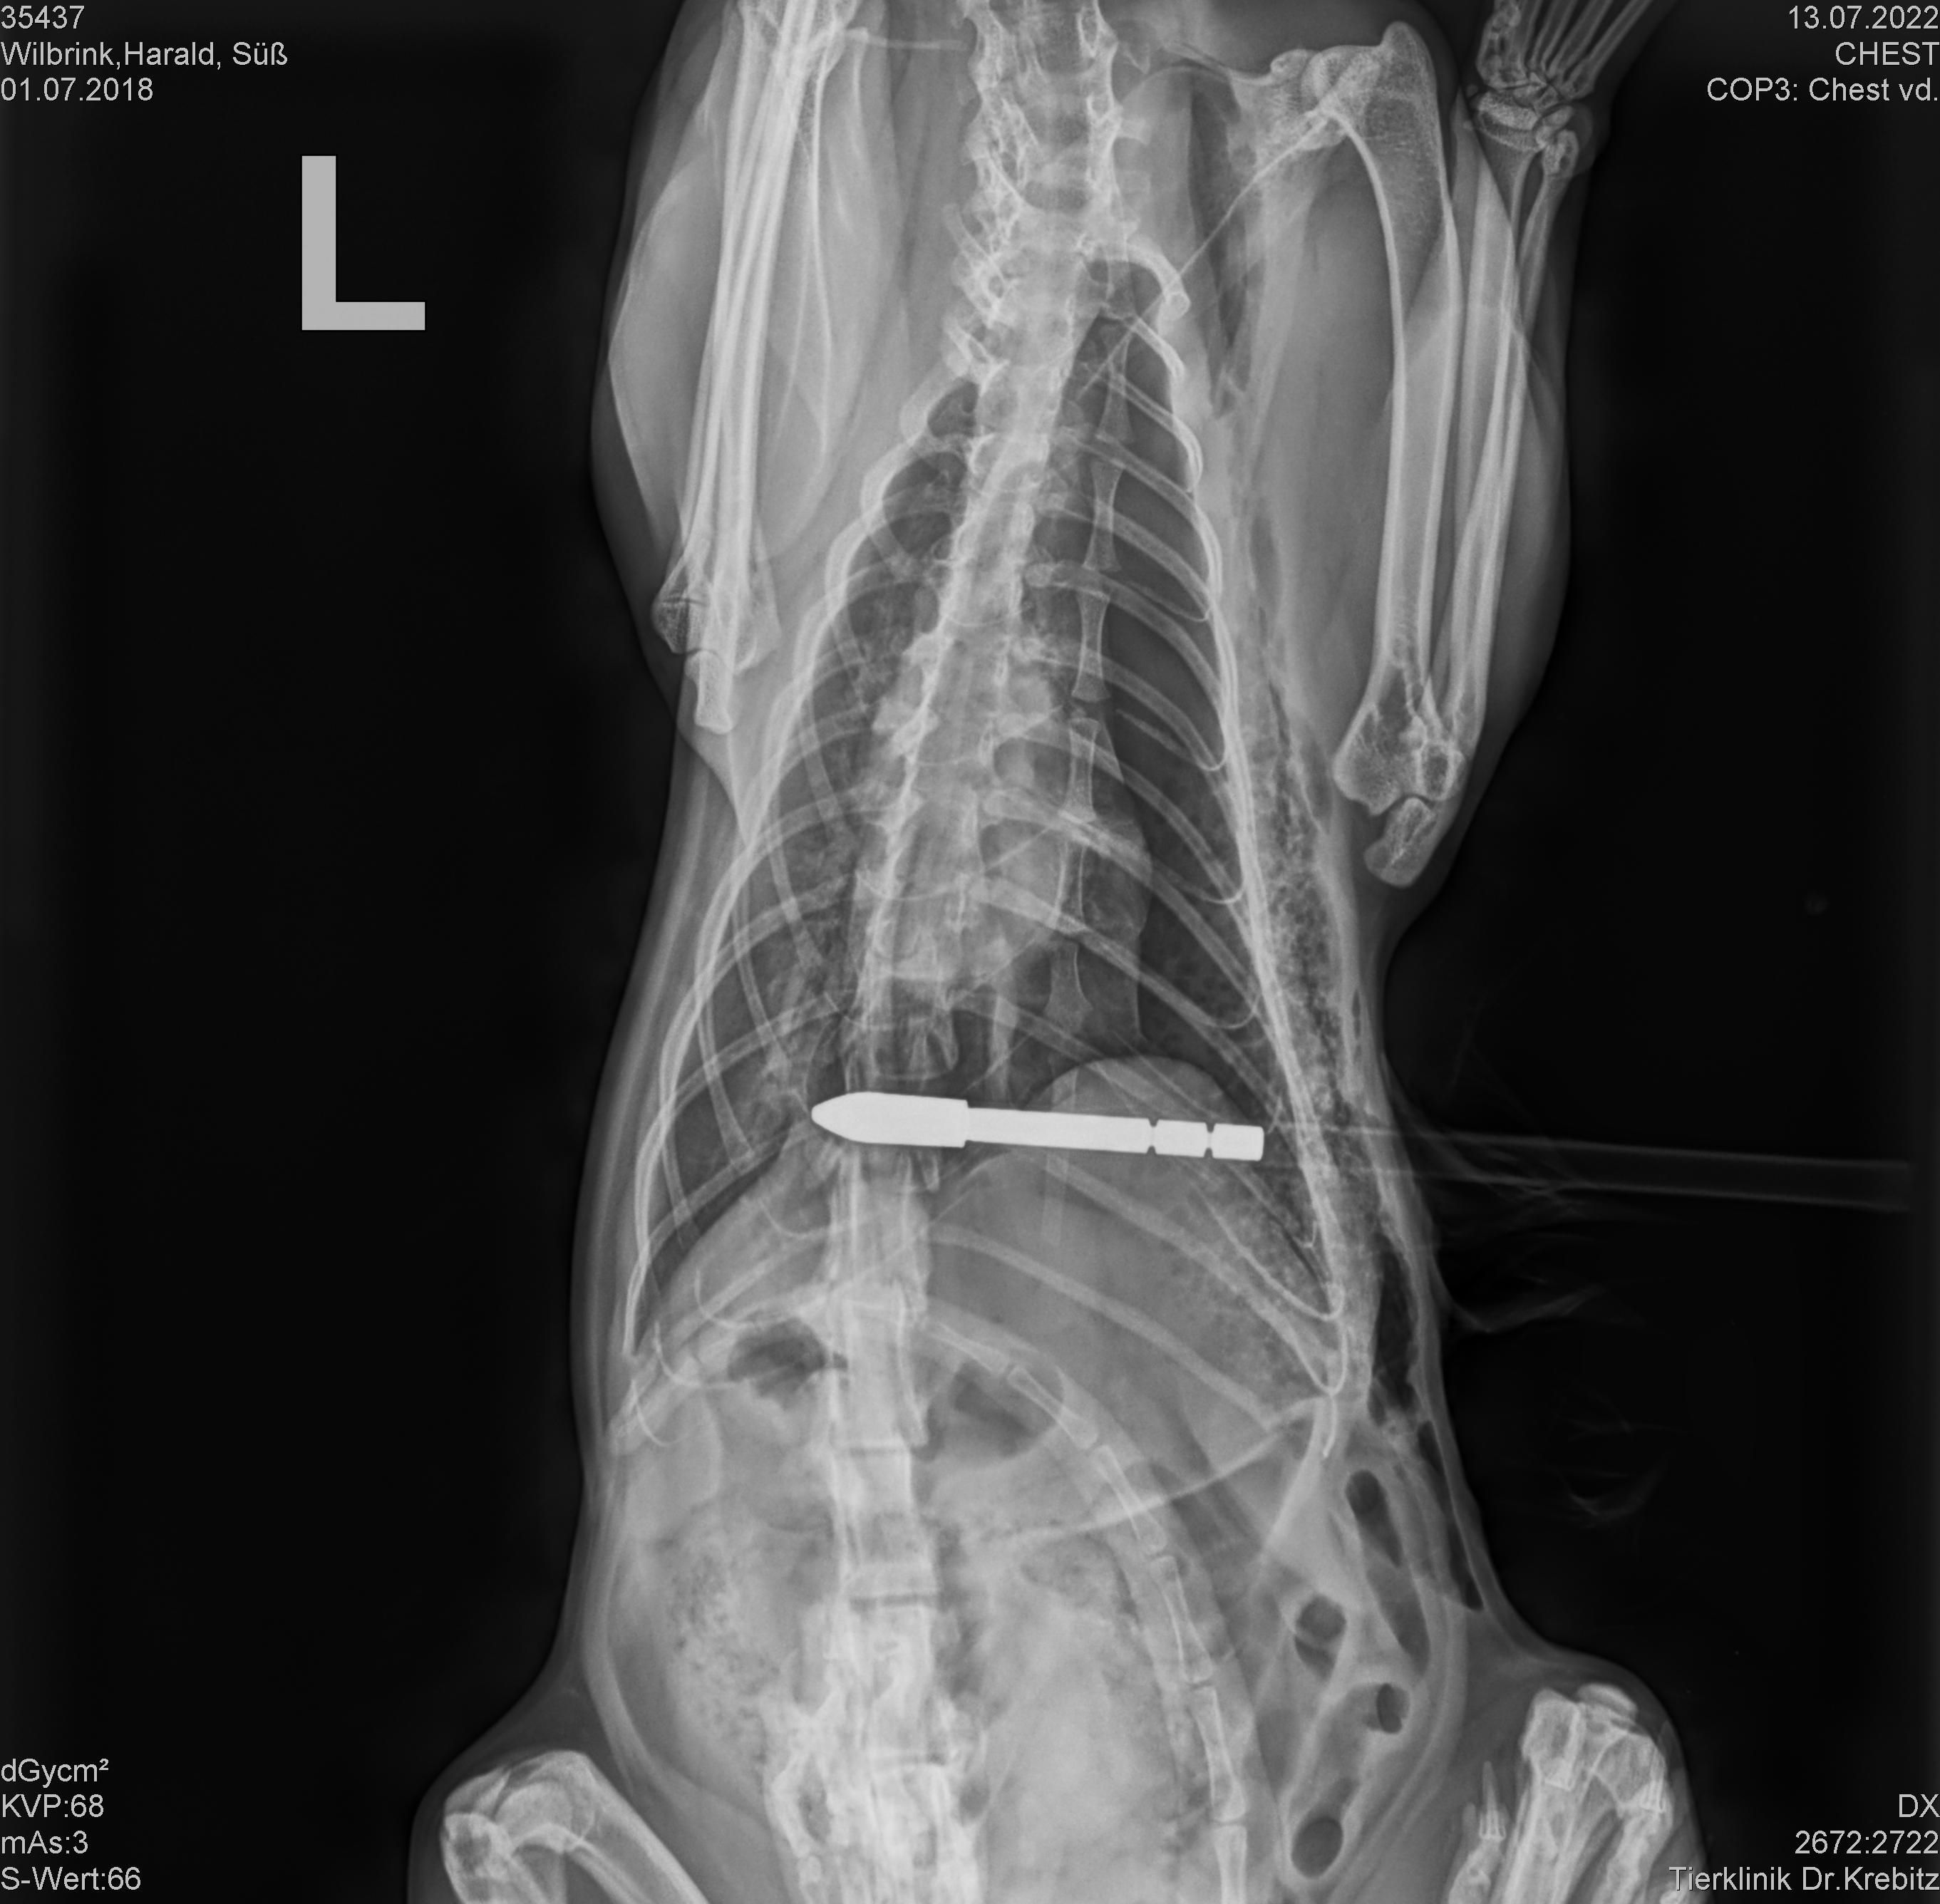

Am 13. Juli 2022 in den Nachmittagsstunden schoss ein bisher unbekannter Täter im Bereich Zmuln, Gemeinde Liebenfels, Bezirk St. Veit an der Glan, mit einem Pfeil auf eine freilaufende Katze.

Der Pfeil durchbohrte die Katze, verletzte diese im Bereich der Lunge und blieb in ihr stecken.

Die Katze wurde in eine Tierklinik in Klagenfurt gebracht und der rund 80 cm lange Pfeil operativ entfernt.